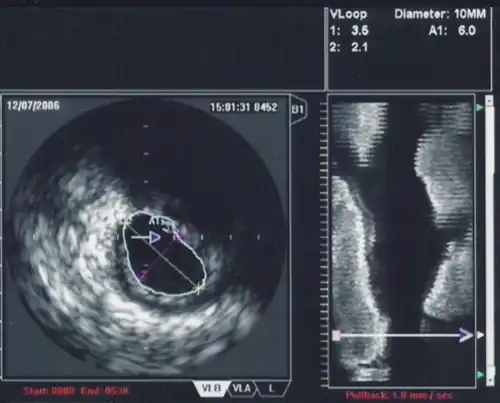

An IVUS image of the ostial left main coronary artery (left). The blue outline delineates the cross-sectional area of the lumen of the artery (A1 in the upper right corner), measuring 6.0 mm2. A two-dimensional mapping of the proximal LAD and left main coronary arteries is shown on the right.